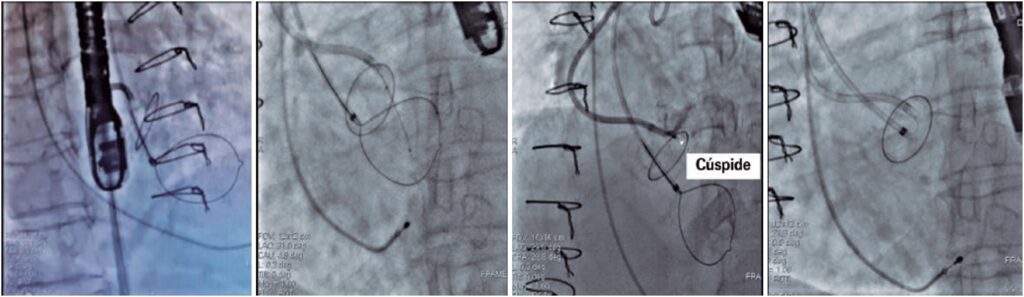

O implante de valva aórtica transcateter é considerado um tratamento padrão para muitos pacientes sintomáticos com estenose aórtica grave. A oclusão da artéria coronária após o implante de valva aórtica transcateter está associada à taxa de mortalidade de até 50%. Neste relato de caso, descrevemos um paciente com disfunção grave da bioprótese aórtica, com alto risco de obstrução coronária após o implante de valva aórtica transcateter. Esse paciente foi submetido ao procedimento BASILICA, seguido do implante de valva aórtica transcateter valve-in-valve. O paciente teve boa melhora e recebeu alta hospitalar 2 dias depois, sem quaisquer sintomas. Ele permanecia assintomático aos 6 meses de acompanhamento.